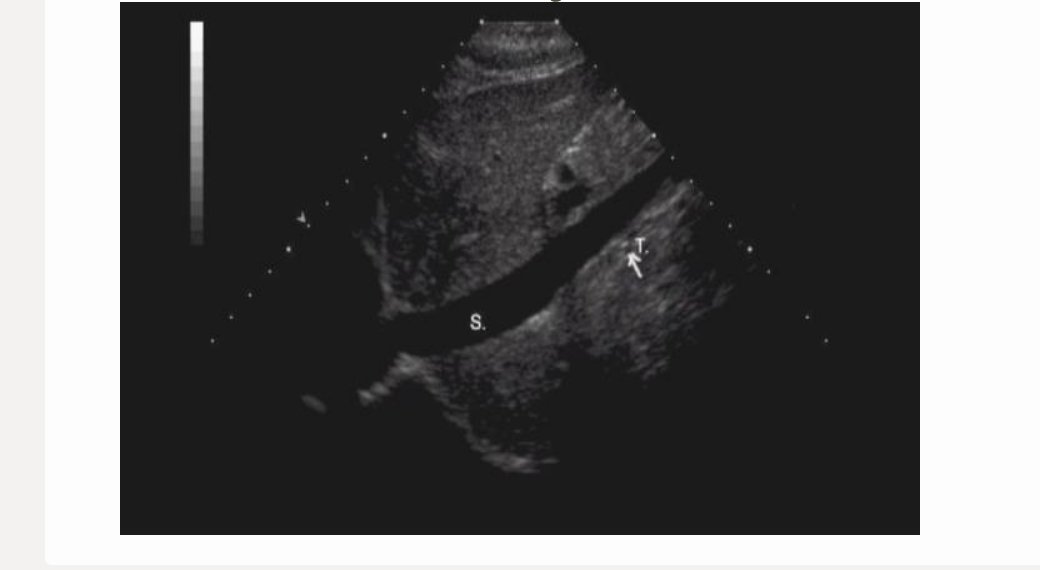

this image is

.

a) incorrect label + diameter

b) correct label; incorrect diameter

c) correct label; correct diameter

d) incorrect label; correct diameter

a. incorrect label + diameter